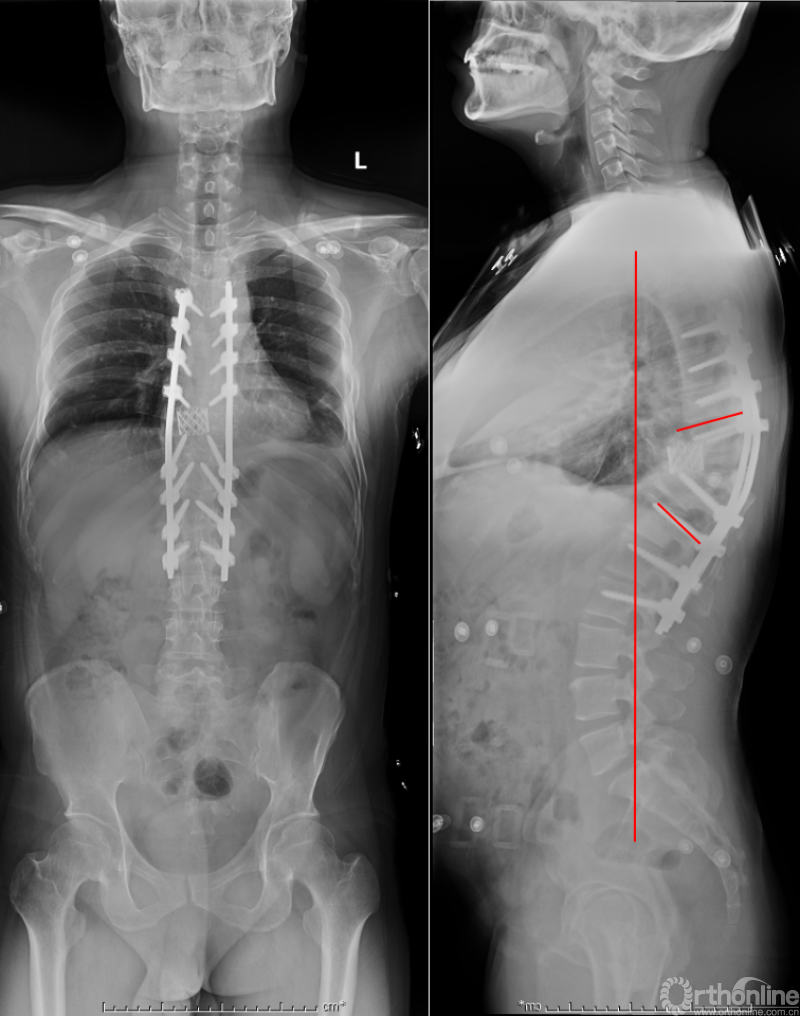

众所周知,脊椎结核后突畸形是结核病严重的后遗症之一。不仅影响患者外表仪容和心理,还可能出现晚发病灶造成截瘫。30多岁的小李就是一位脊柱结核后造成后凸畸形伴截瘫的患者,其畸形角度高达90度。针对此类患者的治疗大多就是截骨矫形,手术创伤大不说,椎体切除后造成的脊柱失稳等一系列后遗症也是令医生和患者担忧的。为解决临床上的这类问题,丁文元教授对传统的PVCR截骨技术进行了简化和改良,即后路单侧截骨部分椎体切除固定矫形术(UPVCR)入路,该技术采用后方单侧截骨,切除部分椎体、相邻椎间盘大部,保留对侧椎弓根及部分椎体,重建置入钛网支撑。随后,丁文元教授通过UPVCR技术对小李实施了手术,经过家人悉心地照顾,小李术后肌力恢复的良好,很快就出院了。三个月复查时竟是自己走路来的,临床疗效让患者及家人很是满意。

患者术后资料

丁文元教授介绍说,UPVCR技术的优势在于手术操作简单,易于掌握,学习曲线短,手术时间短,出血少,神经并发症少;临床应用时极少发生断钉、断棒、不融合的现象,术中保留了良好的血运、植骨床,提供骨生长环境,保证部分骨支撑,术后极少发生矫正丢失,临床效果肯定。